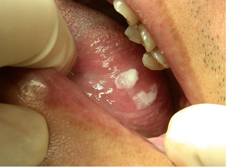

口腔癌的危險因子最重要的就是抽菸、喝酒以及嚼食檳榔,台灣的一篇統計資料中發現同時有吸菸、飲酒與嚼檳榔習慣的人比沒有的人,他的口腔癌罹癌機率多了整整123倍,而單單有嚼食檳榔習慣的人罹癌的機率也比沒有的人多28倍。到底口腔癌有哪些警訊呢?首先,口腔癌有一些癌前病變,包括有白斑症(圖一)、紅斑症、黏膜下纖維化以及疣狀增生(圖二),這些癌前病變皆有機會進一部變成口腔癌。其次,得到口腔癌有哪些症狀呢?

圖一、可見病人舌頭左側邊有明顯的白斑症